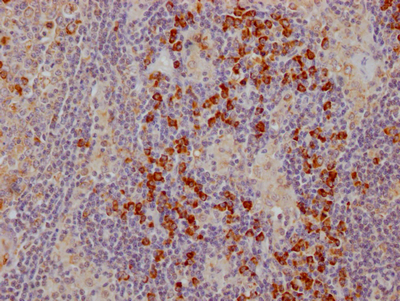

IHC image of CSB-RA213310A0HU diluted at 1:100 and staining in paraffin-embedded human tonsil tissue performed on a Leica BondTM system. After dewaxing and hydration, antigen retrieval was mediated by high pressure in a citrate buffer (pH 6.0). Section was blocked with 10% normal goat serum 30min at RT. Then primary antibody (1% BSA) was incubated at 4℃ overnight. The primary is detected by a Goat anti-rabbit IgG polymer labeled by HRP and visualized using 0.05% DAB.